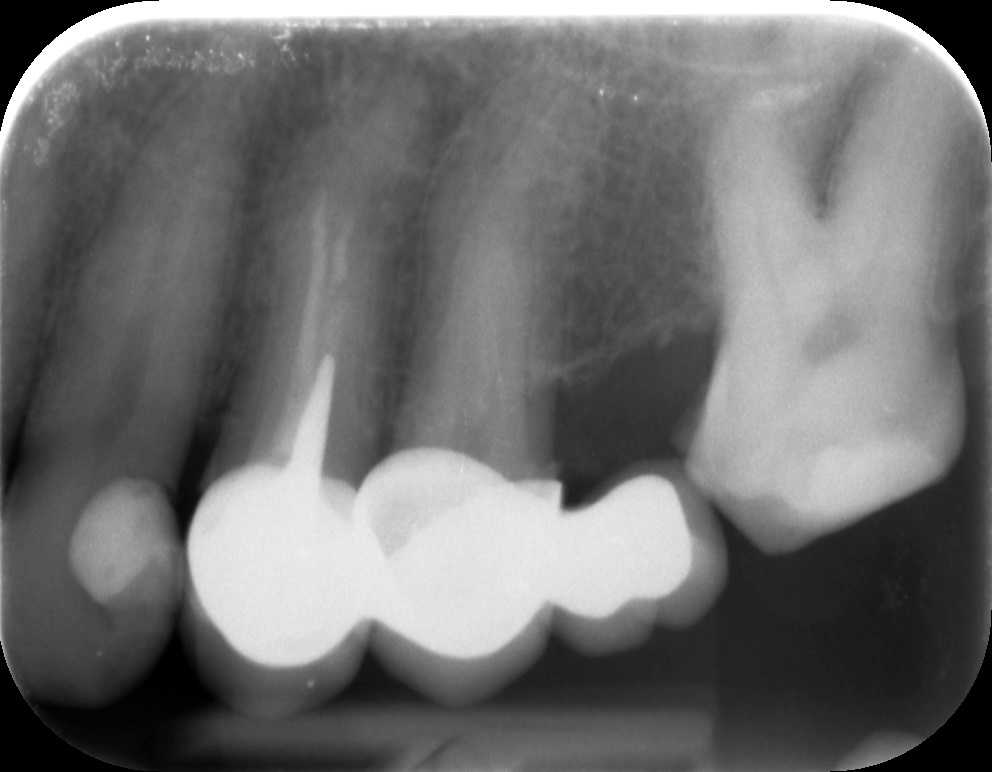

A panorámaröntgent követően készítettünk kisfelvételt is az érintett oldalról. A képen jól látható, hogy a bal felső négyes fog a híd alatt csappal van megerősítve, és a gyökértömés a csatornákban nem ér végig, ennek következtében a gyökércsúcs körül gyulladás alakult ki. A híd levételére, a csap és a gyökértömés mikroszkóppal történő eltávolítására volt szükség ahhoz, hogy a fogat meggyógyítsuk.

mikroszkópos gyökérkezelés előtti állapot